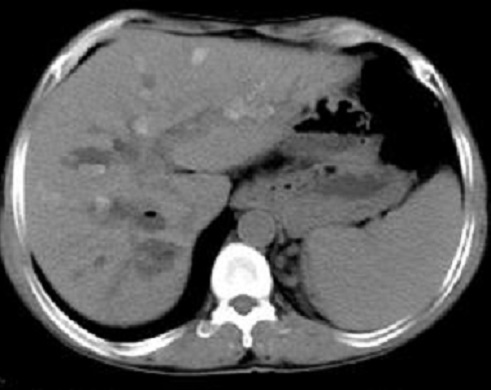

Aspects arrondies

hypodensite a bord irregulier de deux abces

angiocholite situe du foie droit (

fleche rouge ) . Image radiologique TDM avec

de contrast intraveineuse ( C+ ) en coupe

axiale . |